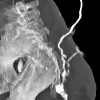

КТ-фистулография

КТ фистулография. Томографическая диагностика, включающая сканирование патологических свищевых путей в кости и мягких тканях. Исследование проводится после предварительной инъекции через свищевое отверстие рентгеноконтрастного вещества. Компьютерная фистулография в стандартных режимах и с объемной реконструкцией используется для диагностики хронического остеомиелита кости. Томограммы определяют размер, направление, форму свищевого прохода, его связь с соседними анатомическими структурами, наличие секвестров и разводов в мягких тканях. КТ-фистулография позволяет отслеживать динамику консервативного лечения, определять метод и объем хирургического вмешательства, делать прогноз.